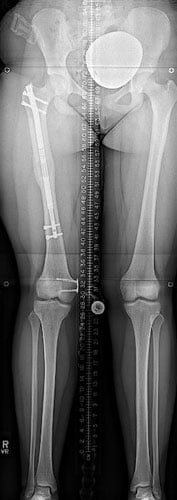

Case #74: Femur lengthening and deformity correction.